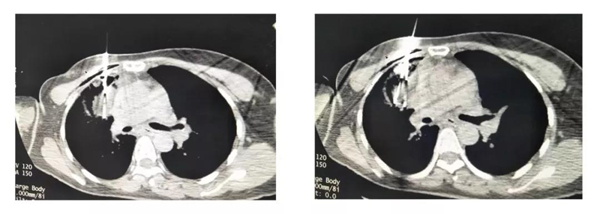

患者40岁女性,8年前因右眼睑板腺癌手术,放化疗后,右侧腮腺粒子植入术后,现肺部转移。因无法手术,综合判断后决定行肺部病灶氩氦刀冷冻消融治疗。因患者病灶有三处,并分列胸骨左右两侧,故术者决定用四刀组合,肺双侧同时穿刺进针,一次消融所有病灶。因为病灶分散,形状不规则,紧邻重要脏器,因此手术难度极大。经过一个多小时的操作、治疗,手术顺利完成。罗凌飞精湛娴熟的氩氦刀消融手术令越南医生赞不绝口,收获满满。

氩氦刀冷冻消融治疗术中

本次手术亮点:

1、双侧同时穿刺

2、一次性冷冻三个病灶